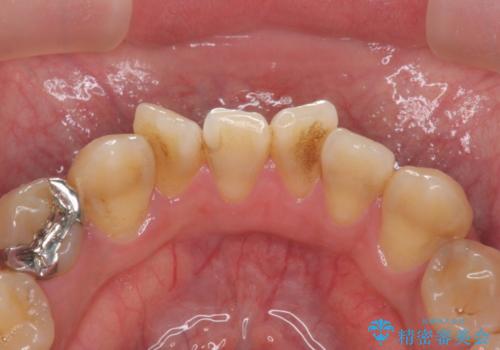

PMTCでコーヒーによる着色を除去。

- コーヒーを毎日飲むため、歯の表面についた着色をとりたいと来院されました。

PMTC(30分コース) 担当衛生士 進藤